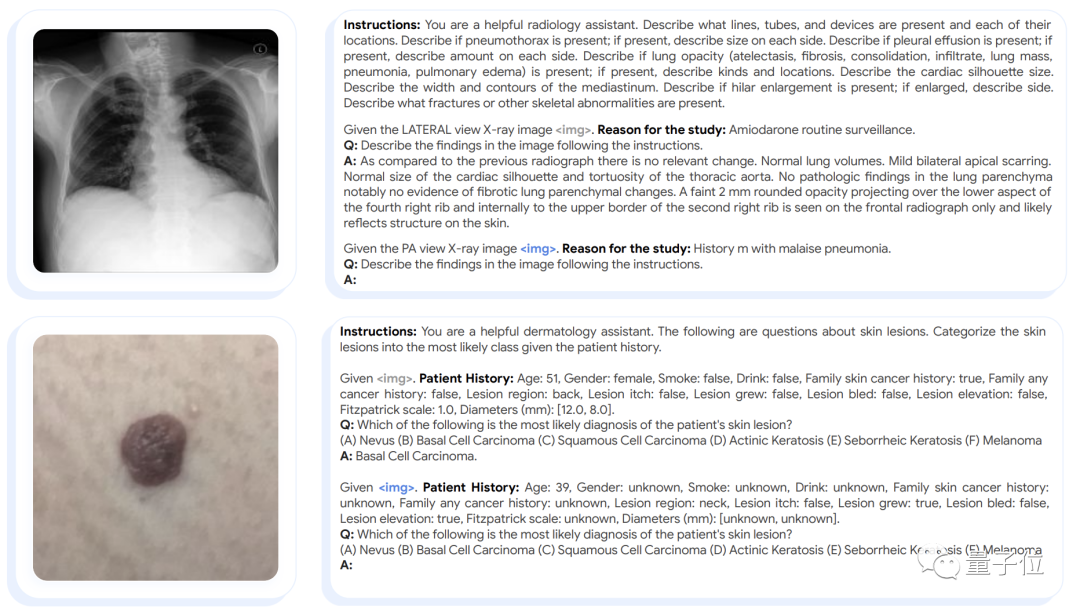

(2)由于谷歌的目标是训练一个通用的生物医学AI模型,使用统一的模型架构和模型参数,用多模式输入执行多个任务。为此,他们为Med-PaLM M提供了特定于各种任务的指令以及一个纯文本的“一次性示例”。

如下图所示的胸部x光解读和皮肤病变分类任务所示,这些指令有一种写提示语的味道,以“你是一个很给力的放射科助理”开头。

(3)训练过程中,作者对PaLM-E进行了端到端的微调。在多模态任务中,图像标记与文本标记交错,以形成对PALM-E模型的多模式上下文输入。对于所有微调任务,多模式上下文输入最多包含1个图像,然而Med-PaLM M能够在推理过程中处理具有多个图像的输入。